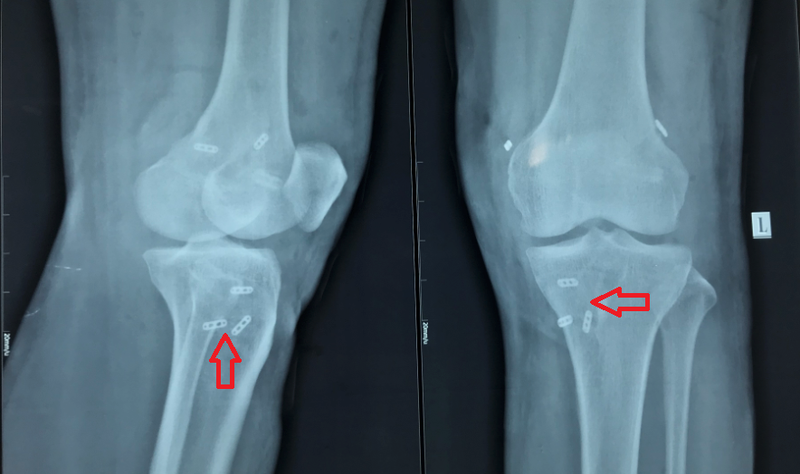

Các bác sĩ đã tiến hành phẫu thuật nội soi tái tạo tất cả 3 dây chằng khớp gối trong cùng một cuộc phẫu thuật. Quá trình phẫu thuật diễn ra thành công, không tai biến. Sau phẫu thuật bệnh nhân ổn định, mang nẹp đùi chân trái và xuất viện sau 5 ngày.

Vị trí các vòng treo gân và vít tự tiêu sau khi tái tạo 3 dây chằng chéo trước, chéo sau, bên ngoài